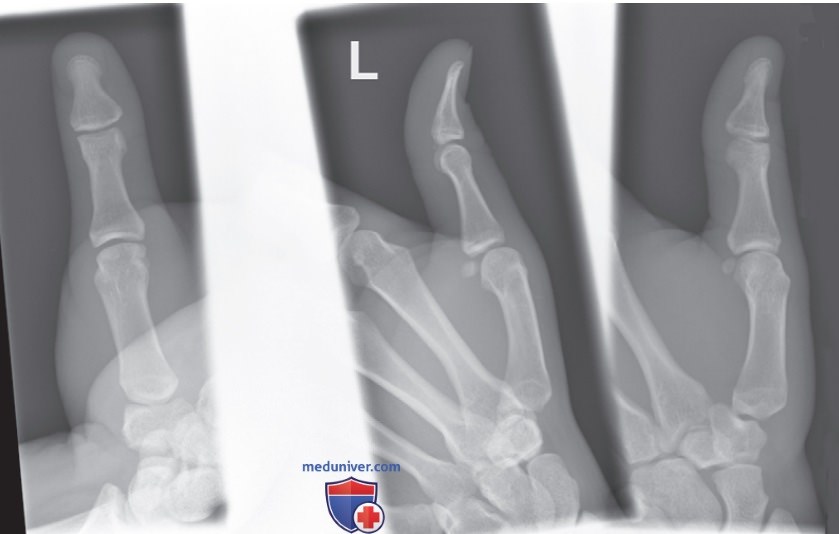

Рисунок 7. Маркировка рентгенограмм одного пальца, выполненных в разных проекциях, но полученных на одном ПИ.

Маркировка и оценка правильности установки маркеров на рентгенограмме

• Если на одном ПИ будет получено несколько проекций одной и той же анатомической структуры, достаточно отметить одну проекцию (рис. 7)